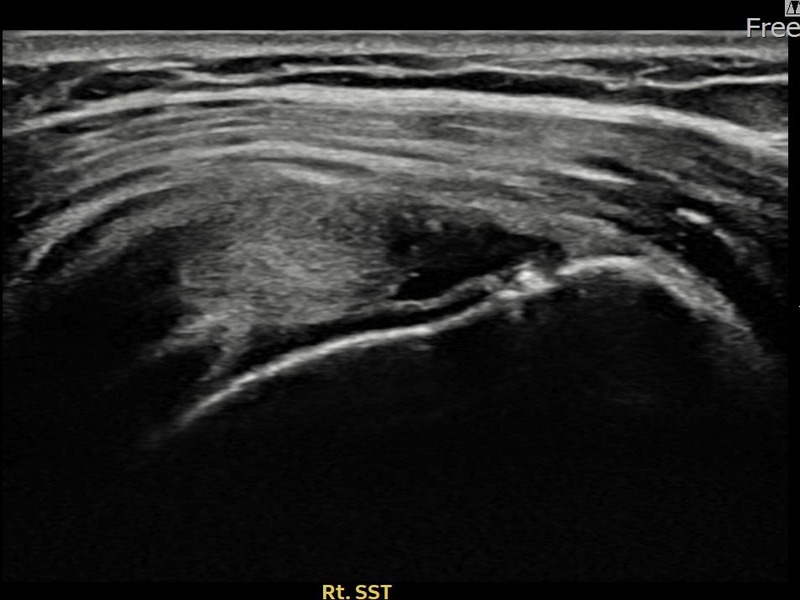

최ㅇㅇ님 · 우측 극상근건 관절면측 부분파열

우측 어깨 통증으로 수면과 일상 동작이 어려워 내원하셨습니다. 초음파 유도 하 축소봉합술 후 힘줄 연속성이 회복되었습니다.

상세 보기 →